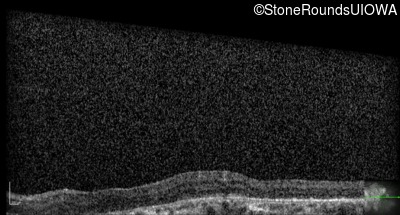

Optical Coherence Tomography - Left - 20/200

Exemplar / OCT Stack